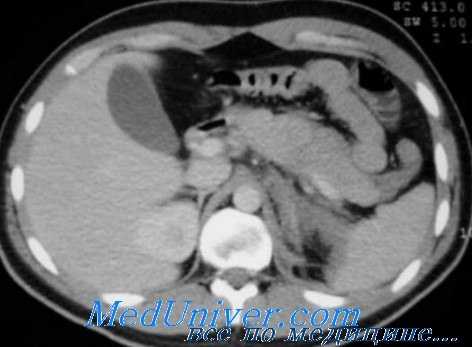

КТ – диагностика повреждений паренхиматозных органов, аорты, очагов кровоизлияний в брюшной полости и забрюшинном пространстве. Использование рентгеноконтрастных веществ (в/в или внутрь) расширяет возможности КТ и позволяет одновременно визуализировать паренхиматозные и полые органы брюшной полости. Повреждения почек и забрюшинные гематомы выявляют с помощью КТ живота, которую нужно провести каждому больному с гематурией и стабильной гемодинамикой (Уровень рекомендации - C)[3]. Необходимость проведения ИВЛ пациенту не является противопоказанием к КТ. Противопоказание - нестабильная гемодинамика пациента. Когда имеется подозрение на повреждение печени/селезенки КТ позволяет исключить повреждения требующие экстренного оперативного вмешательства (Уровень рекомендации - В) [3]. КТ рекомендуется у гемодинамически стабильных пациентов с неоднозначными данными физикального осмотра, сочетанной неврологической травме или множественной экстраабдоминальной травме. При негативном результате КТ пациент госпитализируется для динамического наблюдения (уровень доказательства – I) [5]. КТ позволяет выбрать консервативную тактику ведения у пациентов с солидным характером повреждения внутренних органов (уровень доказательства – I) [5]. У гемодинамически стабильных пациентов ДПЛ и КТ являются дополняющими друг друга методами диагностики (уровень доказательства – I) [5]. КТ не может использоваться как единственный метод диагностики для исключения повреждений кишки, диафрагмы, поджелудочной железы (Уровень рекомендации - В) [3]. КТ БП достоверно идентифицирует гемоперитонеум у пациентов с ТТЖ (Уровень рекомендации - В)[3]. Пероральное введение контраста при КТне является обязательным при диагностике ТТЖ (Уровень рекомендации - В) [3].